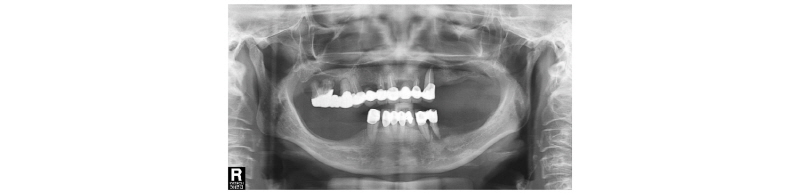

52세 여자 환자가 치아가 상실된 부분에 임플란트 수술과 남아있는 치아의 치료를 원하며 내원하였다. 그러나 남아있는 거의 모든 치아들이 치주질환과 동요도를 보였으며 상악의 경우 모든 치아가 한 개의 브릿지로 묶여 있었다(Fig. 1). 젊었을 때부터 오랜 기간 틀니를 사용하면서 하악 구치부의 경우 잔존 치조골이 거의 없는 상태였다. 단 몇 개의 치아를 살리는 것이 의미 없다고 판단되어 전악 발치를 결정했다. 전치부의 치아가 남아있었기 때문에 틀니를 만들 경우 전치부의 치조골 성형을 상당히 하지 않을 경우 입이 돌출되어 보이는 문제가 생길 수 있었고 환자도 틀니를 원하지 않아 고정성 임플란트 보철을 하기로 하였다. 하지만 하악의 경우 구치부에 임플란트를 식립할 수 없는 상태였으며 수직적 골 거상술은 여러 가지 측면에서 시도하지 않기로 했다.